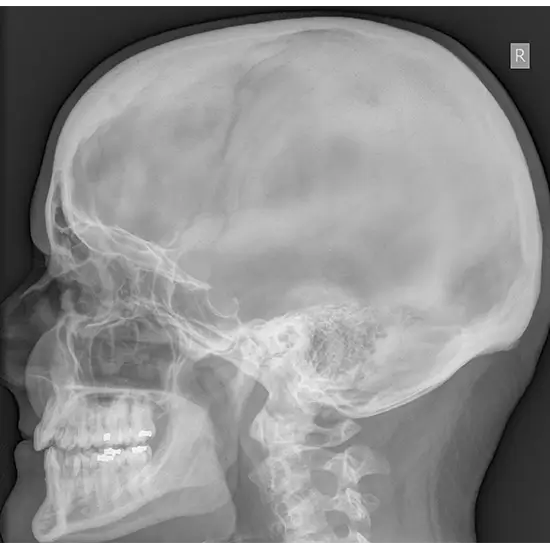

What is an X-ray Mastoid (Right) (Lateral Oblique View) Test?

An X-Ray of the right Mastoid, LAT-Obl test is used to view the mastoid, a skull bone situated directly behind the ear. This bone is composed of air-filled cavities and cells that aid in ear drainage and cleansing.

The physician ordered this test to diagnose any suspected abnormal growth (tumor) in the mastoid bone area and detect infection in the mastoid air spaces.